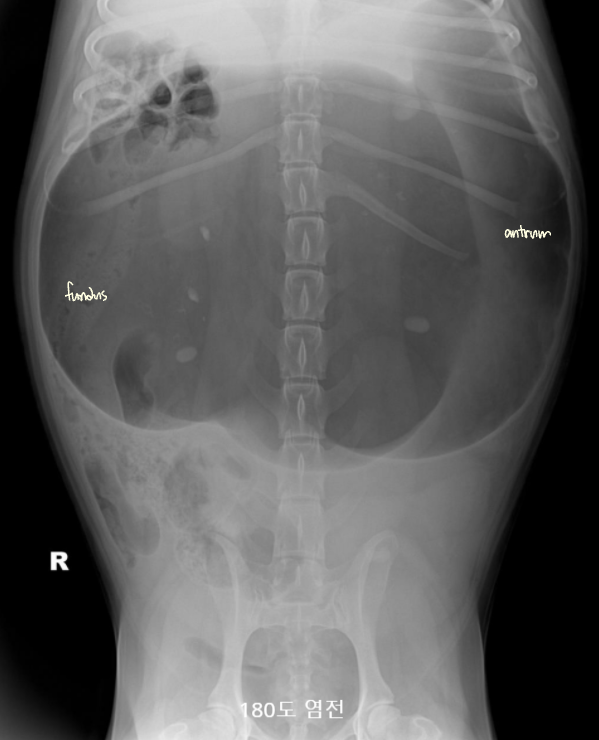

์ํ์ฅ : GD vs. GDV

- ๊ฐ๋ณ์ key point๋ pylorus์ ์์น & ์์ ๋ถํํ(compartmentalization) !

- ์ ์์ ์ธ ์์น๋ ์ธ์ธก์์์ ์๋์ชฝ, ๋ณต๋ฐฐ์์์ ์ผ์ชฝ์ ์์น.

- GD๋ ์๊ฐ ํ์ฅ๋์ด ์์ผ๋, ์์น๋ ๊ทธ๋๋ก.

- GDV๋ ์ฅ์ด ๊ผฌ์ด๋ฉด์ ์์น๊ฐ ๋ฌ๋ผ์ง๋ฏ๋ก, pylorus์ ์์น๊ฐ ์ธ์ธก์์์ ์์ชฝ

| GD | GDV | |

|---|---|---|

| VD | - greater curvature ์ผ์ชฝ(์ ์) * 360๋ ํ์ ์์๋ ์ผ์ชฝ์ ์์น | - greater curvature ์ค๋ฅธ์ชฝ (180๋ ์ผ์ ) - duodenum ์์น๋ ํจ๊ป ๊ผฌ์ |

| RL | - pylorus๊ฐ ์๋์ชฝ(์ ์) | - pylorus ์์ชฝ - ์์ ๋ถํํ(compartmentalization) : ๋ถ๋ฐฉ ํ์ธ - gastric band (soft tissue) ๊ด์ฐฐ |

![]() ![]() | ![]() ![]() | |

[๋ถํํ]![]() ![]() |